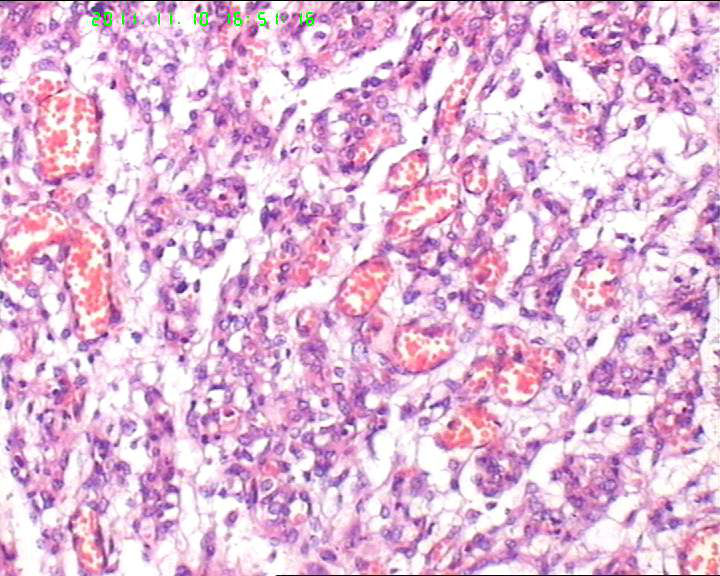

19岁,停经33周,前置胎盘,剖宫产。胎盘母体面可见一灰褐色结节,直径约5.5cm,包膜完整,切面实性,质略嫩。

典型的绒毛膜血管瘤

典型的胎盘毛细血管瘤,发病率约1%,前一阵刚遇到一例。

毛细血管瘤,胎盘常见的肿瘤